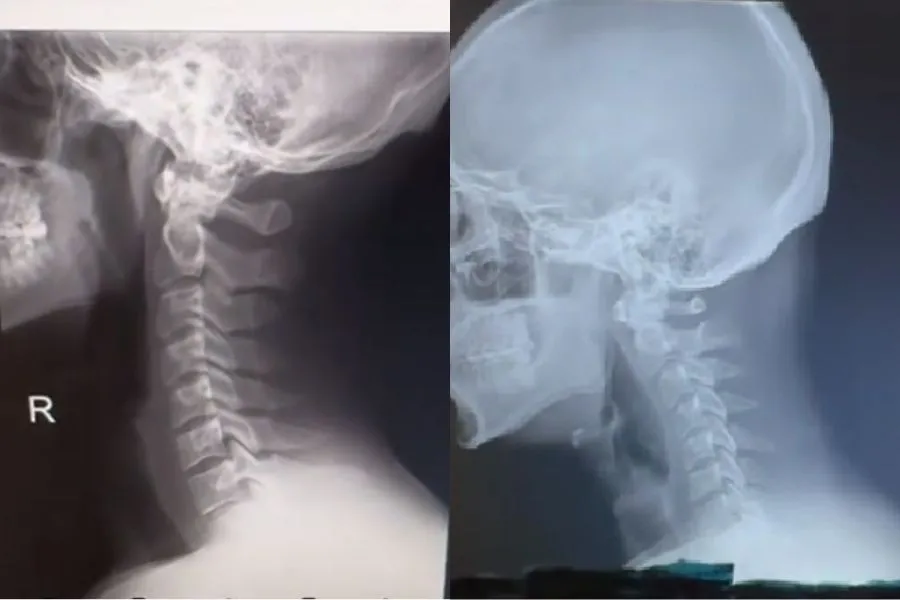

CUELLO TECNOLÓGICO. Una comparación de una columna vertebral normal versus la de una persona joven afectada por la tecnología./CAPTURA DE PANTALLA

El doctor y quiropráctico estadounidense Jake Boyle suele compartir contenido de anatomía en TikTok (@desmoineschiro) y en uno de sus videos el especialista compara una columna vertebral normal con un cuello tecnológico. La publicación se viralizó. "Las columnas tienen una inclinación normal hacia atrás en la zona del cuello, pero hoy en día la mayoría de los pacientes jóvenes que vienen a la clínica se ven como en la segunda foto. Esa deformación no debería comenzar a producirse hasta la vejez, pero la tecnología está cambiando eso", expresó en el video.

El uso intensivo de pantallas, especialmente de dispositivos móviles, está directamente relacionado con estos problemas. Tanto es así que se ha acuñado el término "cuello tecnológico", tal como lo reporta The New York Post. Esta afección se refiere a una curvatura en la parte superior de la columna causada por años de mala postura, atribuida a la costumbre de inclinarse hacia las pantallas.